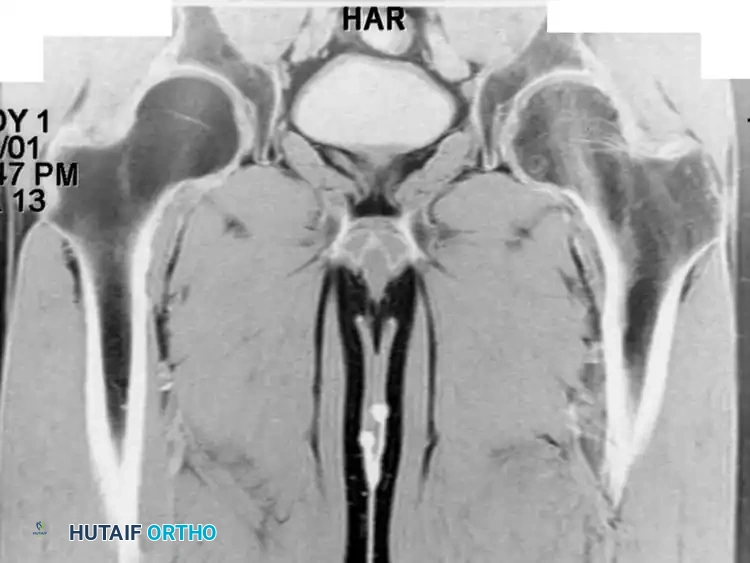

Fig. 20-21: Paget disease of the left proximal femur in a 45-year-old man. (A) Anteroposterior radiograph shows markedly coarsened trabeculae and cortical thickening. (B) Bone scan demonstrates intensely increased radiotracer uptake in the affected proximal femur.

Bone scintigraphy (Technetium-99m) is exquisitely sensitive, showing intensely "hot" lesions. Occasionally, the combination of aggressive plain radiographic features and a positive bone scan may mimic a primary bone sarcoma. In these instances, MRI is an invaluable diagnostic tool; despite the chaotic remodeling, the marrow signal in uncomplicated Paget disease typically remains normal (isointense to fat).